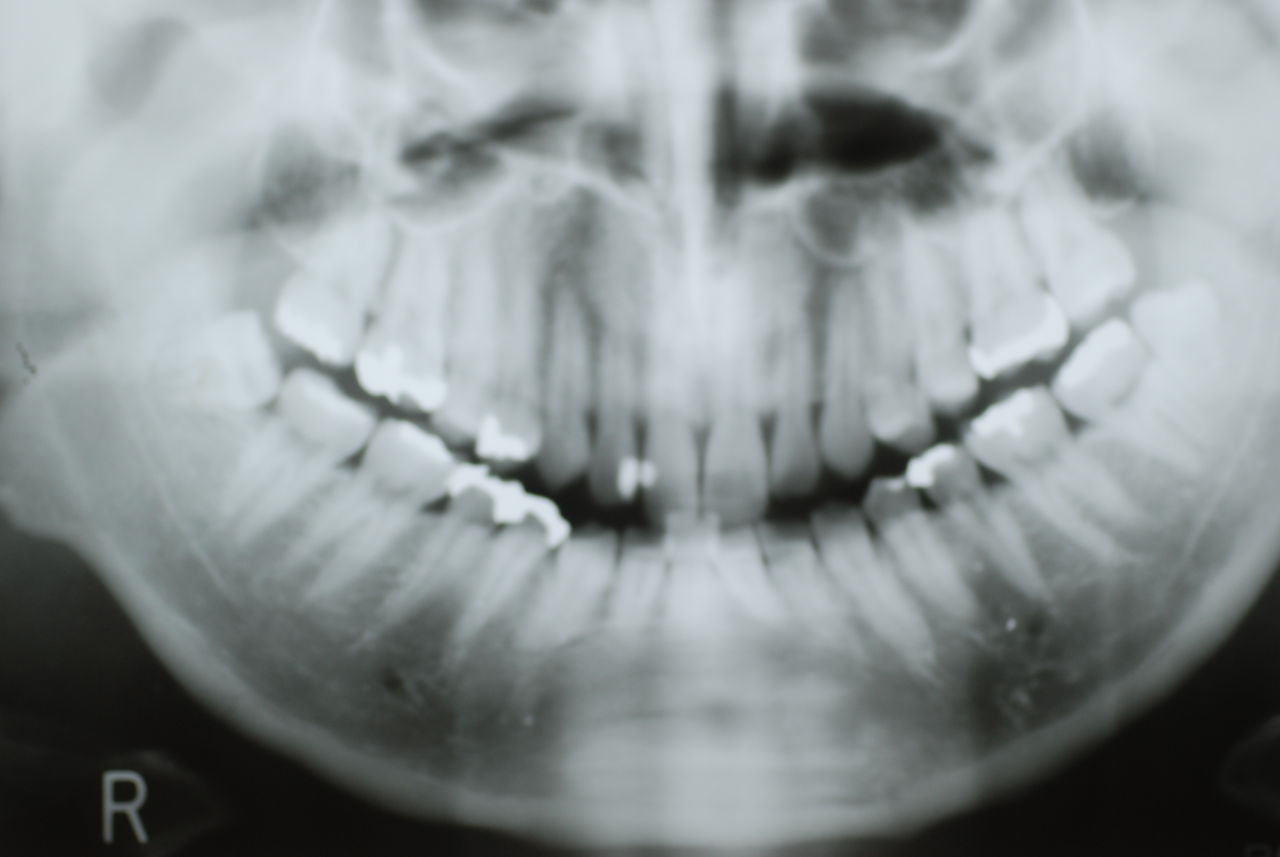

隣の14歳大臼歯がひどい虫歯になり治療不可能になりつつある状態のレントゲン